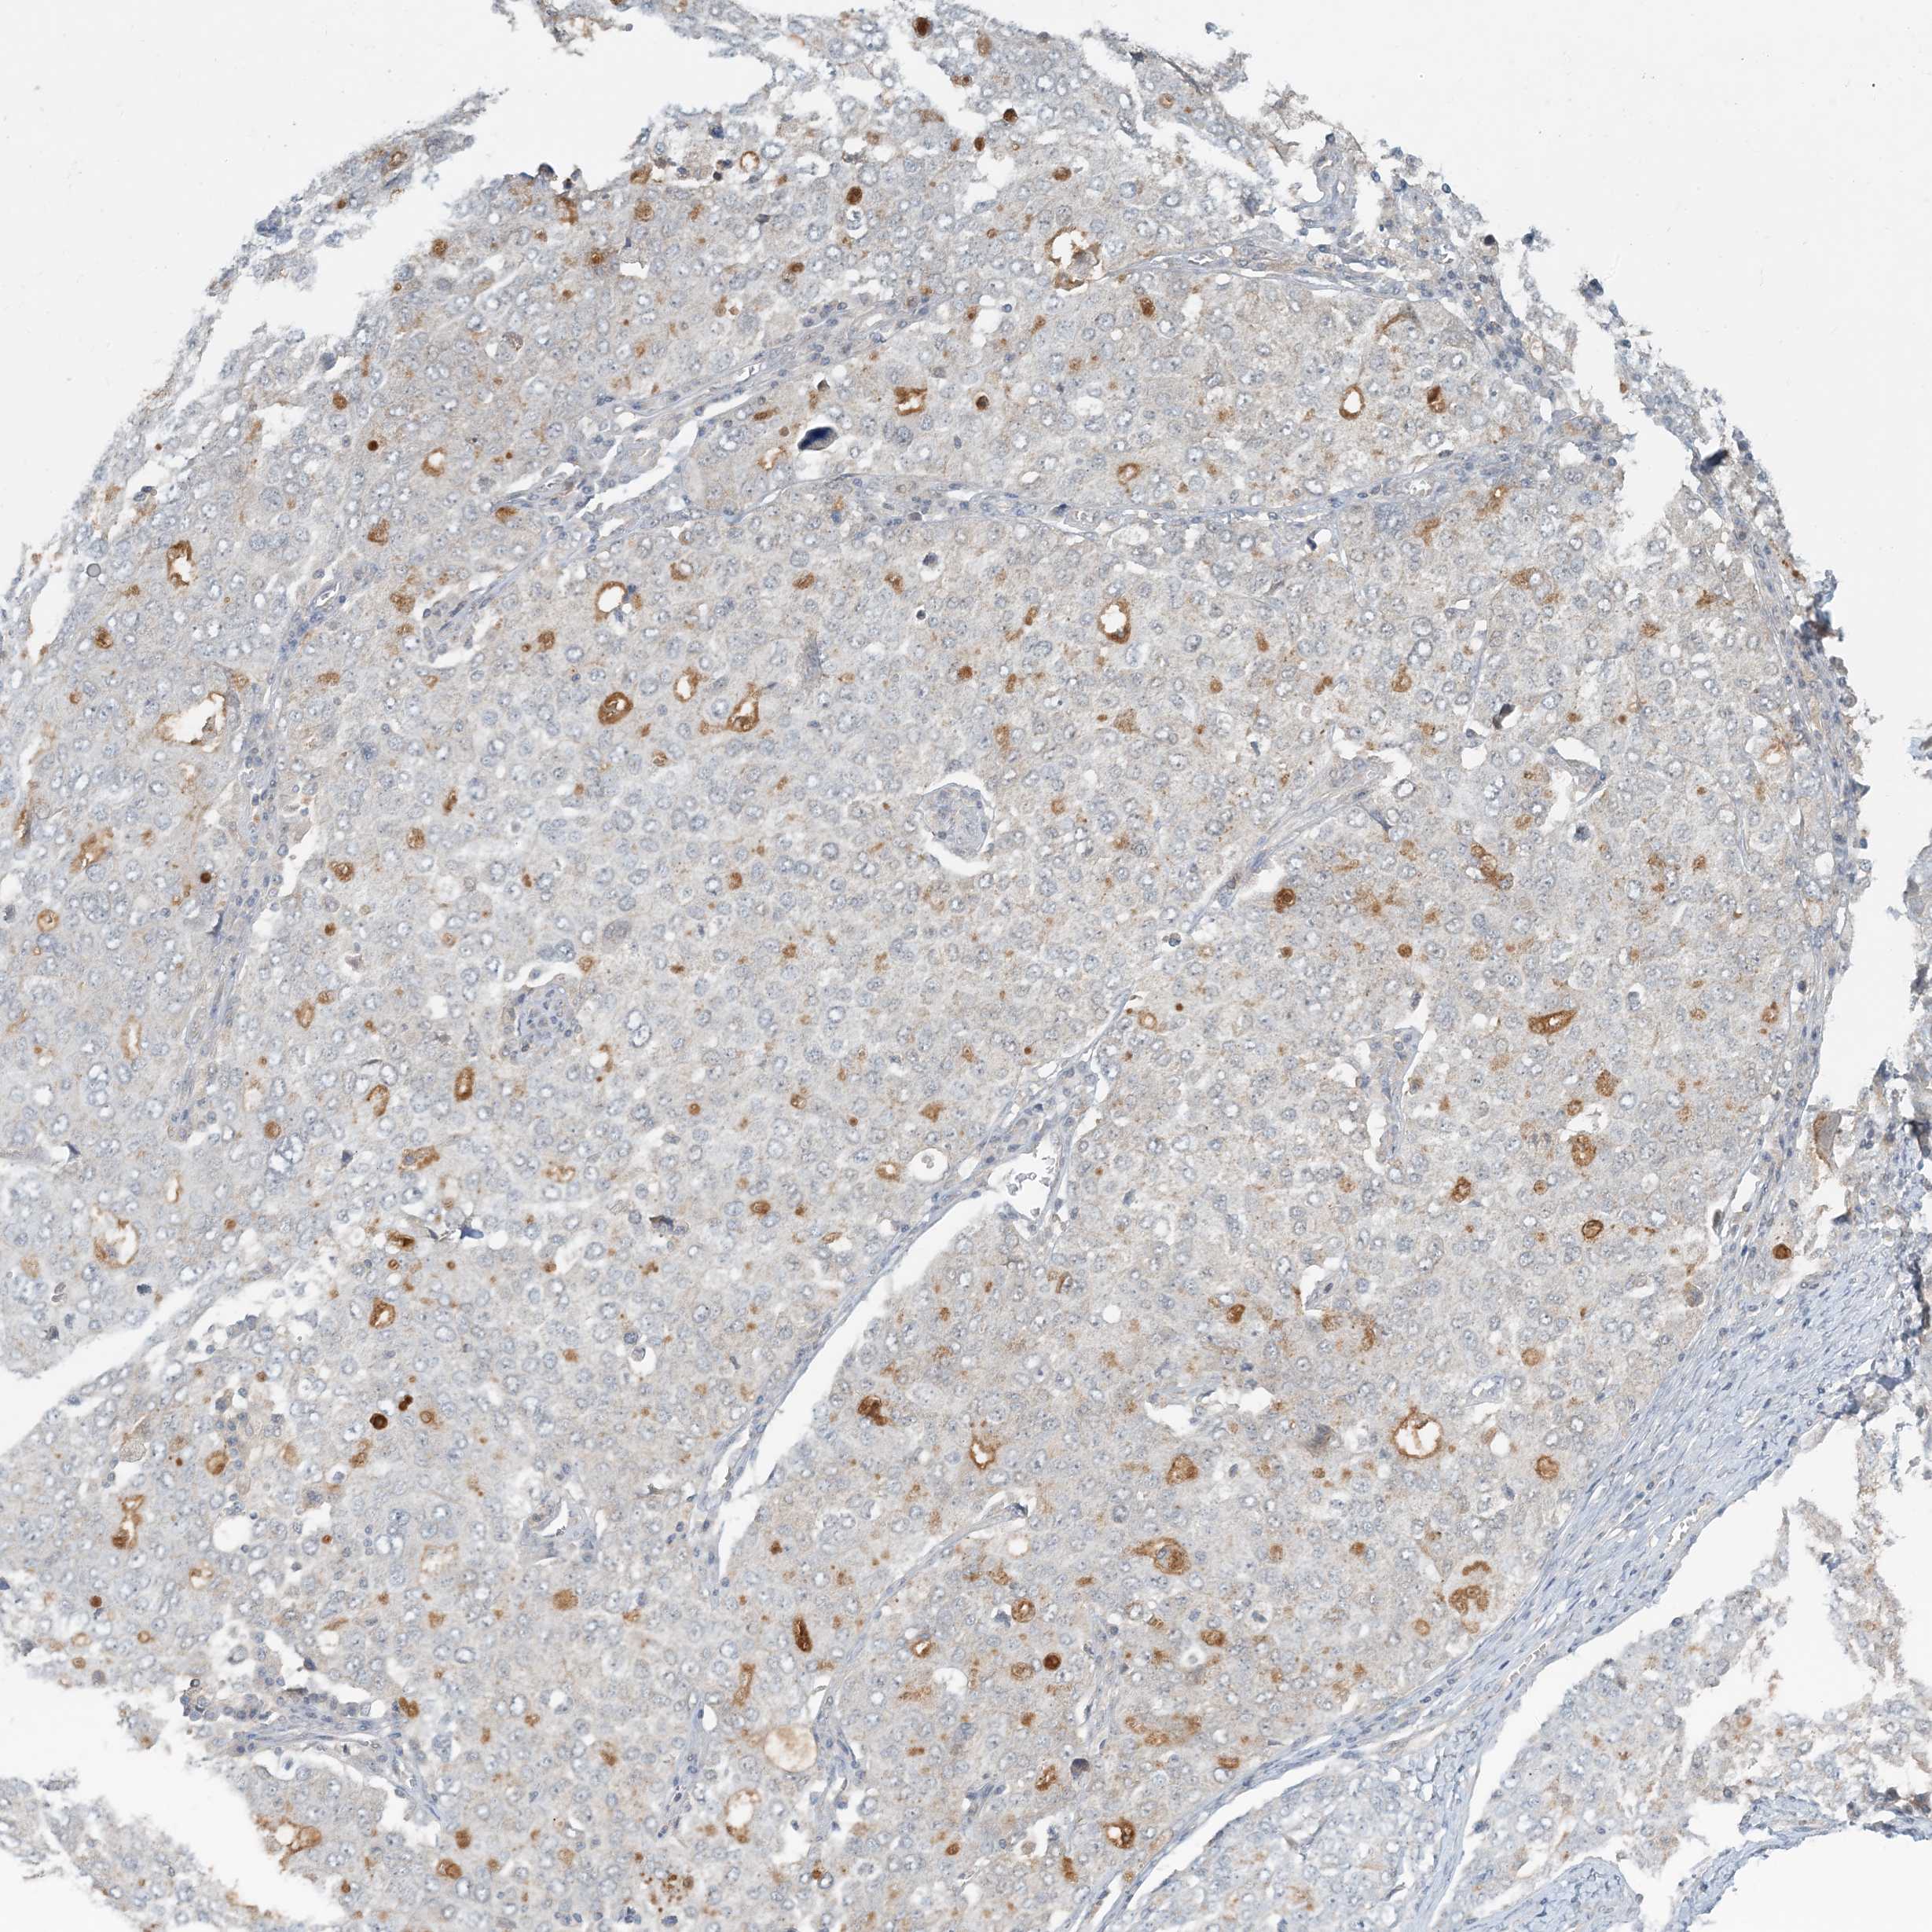

OVARIAN CANCER - Protein expressioni

A mouse-over function shows sample information and annotation data. Click on an image to view it in a full screen mode. Samples can be filtered based on level of antibody staining by selecting one or several of the following categories: high, medium, low and not detected. The assay and annotation is described here.

Note that samples used for immunohistochemistry by the Human Protein Atlas do not correspond to samples in the TCGA dataset.

Antibody stainingi

Antibody staining in the annotated cell types in the current human tissue is reported as not detected, low, medium, or high, based on conventional immunohistochemistry profiling in selected tissues. This score is based on the combination of the staining intensity and fraction of stained cells.

Each image is clickable and will lead to virtual microscopy that enables deeper exploration of all samples and also displays staining intensity scores, fraction scores and subcellular localization as well as patient and tissue information for each sample.

Antibody HPA034785

Antibody HPA034786

Cystadenocarcinoma, serous, NOS

Carcinoma, endometroid

Cystadenocarcinoma, mucinous, NOS

Carcinoma, NOS